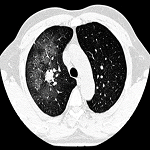

Le signe du halo et l´aspergillose pulmonaire angio-invasive

Pihou Gbande, Kwokwo Kafupi Pacifique

PAMJ-CM. 2022; 10: 9. Published 22 September 2022